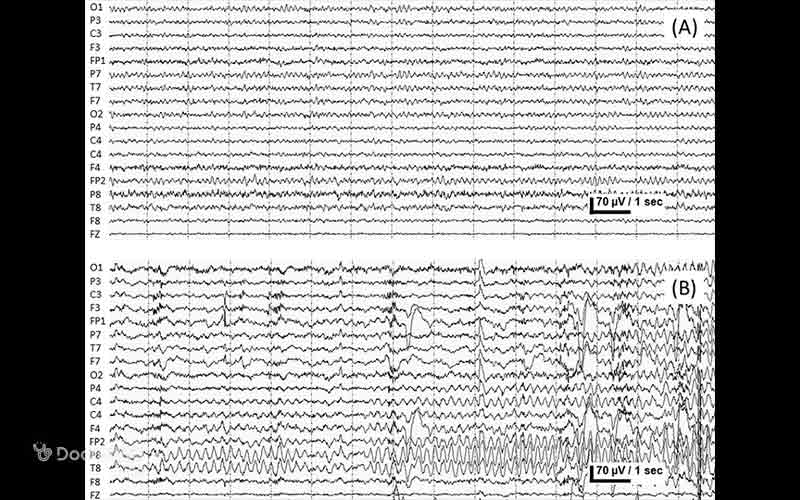

2. عکس نوار مغز صرع و تشنج

سیگنالهای EEG در عکس نوار مغز تشنجی معمولاً به چهار حالت طبقهبندی میشوند:

- حالت قبل از تشنج: چند دقیقه قبل از وقوع تشنج، فعالیت غیرطبیعی مغز دیده میشود.

- حالت تشنج: هنگام وقوع تشنج، امواج تیز و اسپایکها به شدت افزایش مییابند.

- حالت پس از تشنج: پس از پایان تشنج، فعالیت مغز به تدریج به حالت پایه بازمیگردد.

- حالت بین تشنجها: در فواصل زمانی بین تشنجها، فعالیت مغزی پایه همچنان غیرطبیعی بوده و شواهد پنهان از اختلال عصبی نشان میدهد.